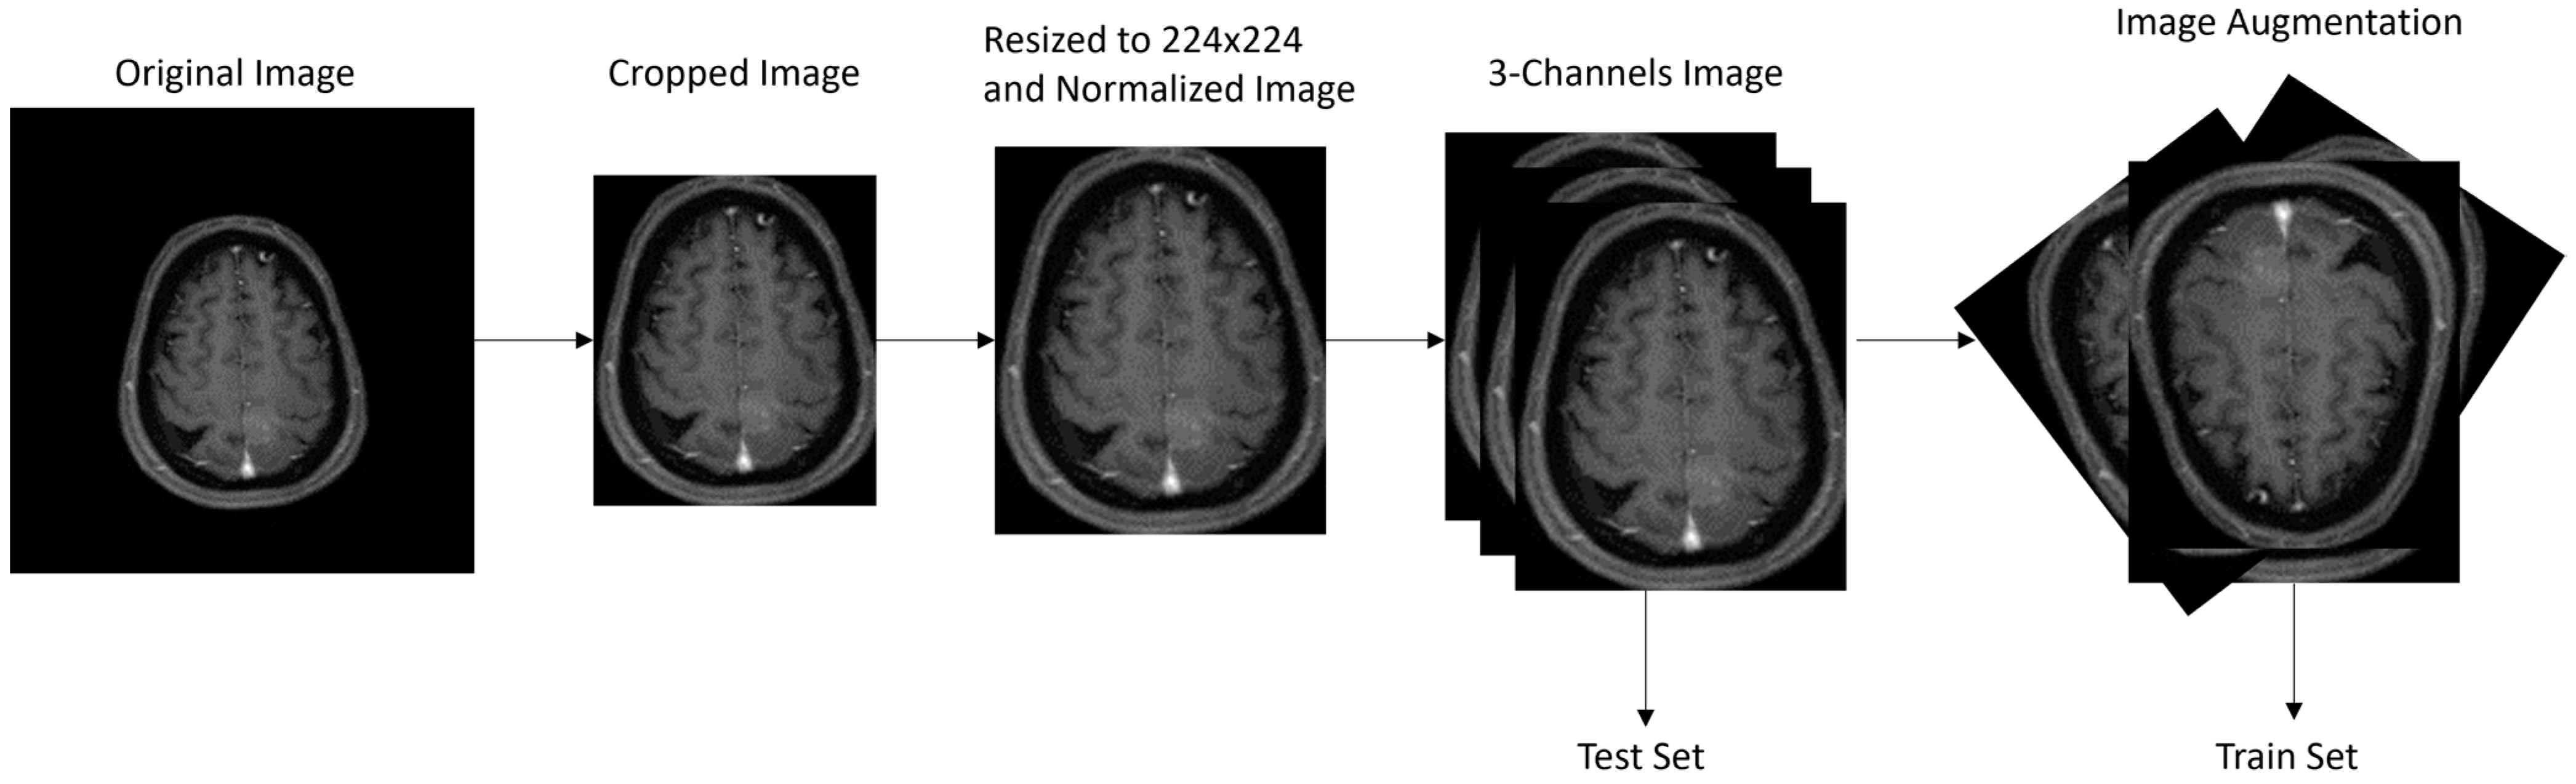

2.2. Image Preprocessing